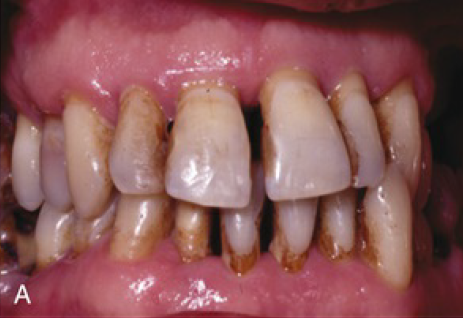

Jau 1960 metais buvo nustatyta, kad periodontas labiausiai kenčia dėl susikaupusių apnašų. Žmogaus burnoje galima aptikti maždaug šeši šimtus rūšių bakterijų: dalis jų neturi neigiamo poveikio sveikatai, tačiau kai kurios bakterijos gali sukelti įvairius negalavimus. Jei nesirūpinama tinkama dantų ir dantenų higiena, ima kauptis apnašos, iš kurių vėliau susiformuoja dantų akmenys. Nors patys dantų akmenys nesukelia periodonto ligų, tačiau jų šiurkšti ir porėta tekstūra sudaro palankesnes sąlygas kauptis bakteriniam apnašui. Ilgainiui tarp dantų ir dantenų atsiranda tarpeliai, kurie vadinami dantenų kišenėmis. Atsiradus šiai patologijai bakterijos ima dar sparčiau daugintis, todėl išsivysto uždegimas, apimantis gilesnius audinius ir žandikaulio kaulą. Ligos eigai įtakos turi imuninė sistema – jei periodontitas nėra laiku gydomas, šis susirgimas didina širdies susirgimų riziką, gali neigiamai paveikti diabeto eigą ar lemti priešlaikinį gimdymą.

Periodontologas visada vertina paciento burnos būklę ir sudaro individualų gydymo planą. Jei nėra diagnozuojami negrįžtami pakitimai, kartais tereikia atlikti profesionalią burnos higieną ir nuvalyti viršdanteninius ir podanteninius akmenis. Jei procesas pažengęs atleikamas giluminis valymas (dantenų kiuretažas) su uždegimo pažeistų dantenų konservatyviu pašalinimu. Ypatingai sunkiais atvejais atliekama atliekama lopo operacija, kai pašalinamas didelis kiekis pažeistų dantenų, žandikaulio defektai gali būti užpildomi kaulo užpildais. Šiuolaikinė periodontologija užtikrina, kad pacientui atliekamos procedūros nesukels pernelyg didelio diskomforto – visuomet yra taikomas nuskausminimas.